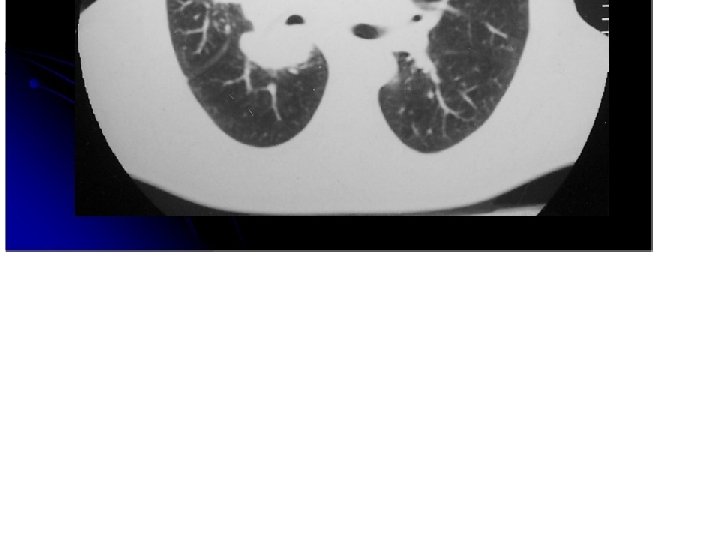

Enfisema centrolobulillar. Infiltrados intersticiales. Masa parahiliar izqueirda.

Masa hiliar lobulada con infiltrados interticiales y compromiso del bronquio intermedio. Atelectasia .